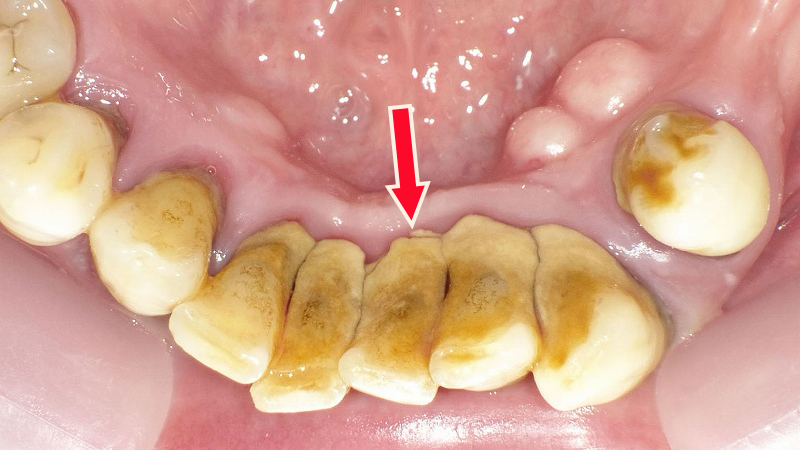

🦷 ⚪白い歯石(歯肉縁上歯石)

📍よく見られる場所:下の前歯の裏側

白い歯石は、特に下の前歯の裏側にべったりと付着することが多いです。

💧付着しやすい理由

この場所は、舌下腺と顎下腺が合流する唾液の開口部があり、唾液中のリン酸やカルシウムが豊富に供給されるため、歯垢と混ざって歯石が形成されやすくなります。

🧹自然に取れることもあるが要注意

大量に沈着した場合、歯ブラシやフロス、歯間ブラシで一部が自然に取れることもあります。→ 一部が取れても歯石は完全には除去されず、歯科での専門的なクリーニングが必要。